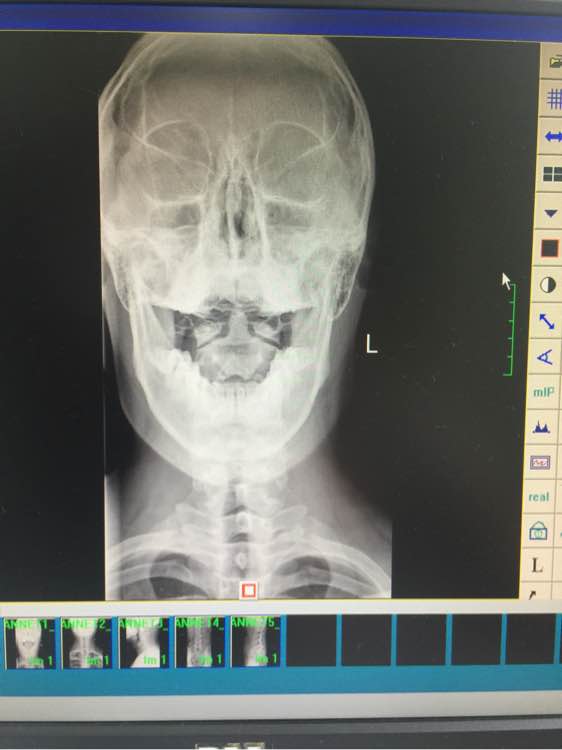

求吧友们帮我看看,寰枢椎关节半脱位,供血不足

站不稳,坐不稳,走不稳, 做什么都飘飘的,走路不平衡,躺着还有塌陷的感觉 除了早上醒来 舒服点,越到下午越来越严重, 感觉无时无刻人就像在船上 左右摇晃的 偶尔更换体位 耳朵鼓鼓的 (这是国庆最严重时候 现在还是晕,没那么晕了,但还是没好 以下一直影响生活到现在)尿尿要扶墙,洗澡不敢洗太久 靠着墙,刷不了牙,刷牙晃动脑袋也更晕,有时候晚上坐着就犯晕,血压高,145 95以上 躺着血压就正常

寰枢椎还好,问题出在整个颈椎上,慢慢养,磁共振如果压脊髓就去手术